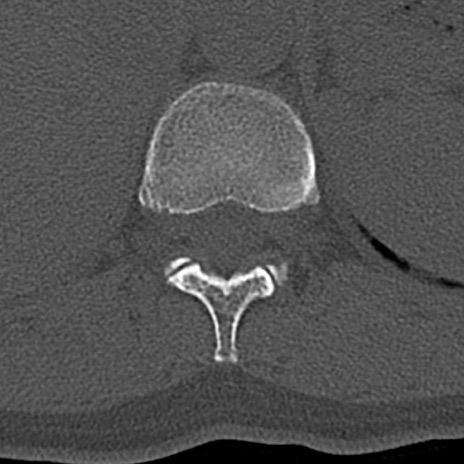

腰椎CT

横断像と矢状断像